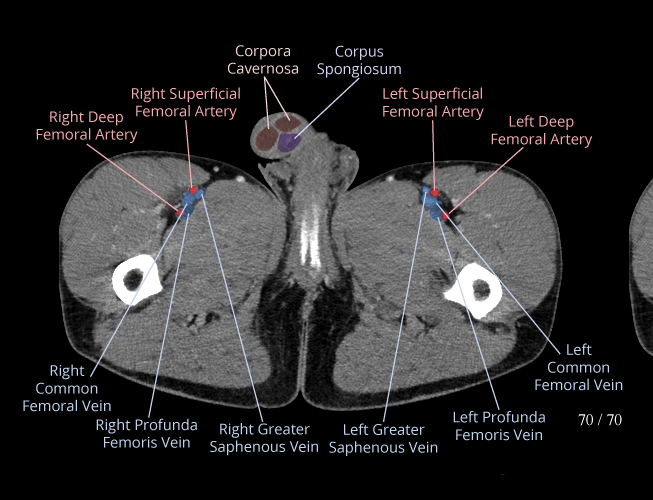

Pelvis

Covers pelvic MRI anatomy.